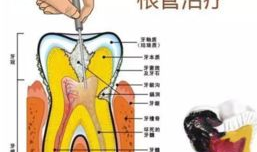

根管治疗视频,从视频学习根管治疗技巧与流程

最近是不是牙齿疼得你坐立不安,连笑容都变得苦涩了呢?别担心,今天就来给你揭秘一下那个听起来有点吓人的根管治疗,让你对这个过程有个...